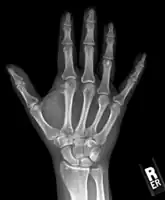

Medical imaging usually shows a well-defined wide-based bony growth on the surface of bone.[5] It can be pedunculated and irregular, giving it a "bizarre" appearance, and is not connected to underlying bone.[2]

X-ray hand, BPOP 2nd metacarpal

X-ray hand, BPOP 2nd metacarpal (side view)